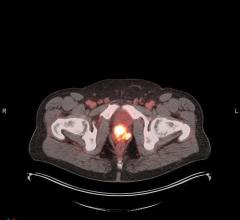

Nov. 18, 2025 — Siemens Healthineers positron emission tomography (PET) radiopharmaceutical companies PETNET Solutions ...